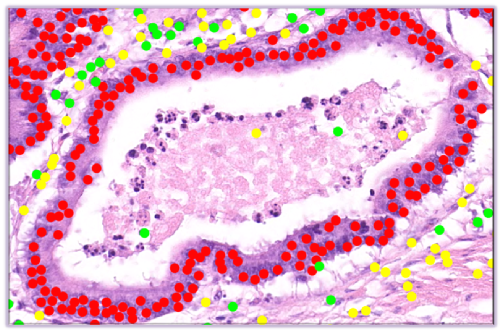

Image: Microscopic landscape of various types of cells - including tumour cells (in red). Click image for high-res.

Scientists at the University of Warwick’s Tissue Image Analytics (TIA) Laboratory - led by Professor Nasir Rajpoot from the Department of Computer Science - are creating a large, digital repository of a variety of tumour and immune cells found in thousands of human tissue samples, and are developing algorithms to recognize these cells automatically.

UHCW is annotating the digital pathology images to help inform the model. The aim is to create a model that will eventually be useful in many types of cancer - creating more objective results, lowering the risk of human errors, and aiding oncologists and patients in their selection of treatments.